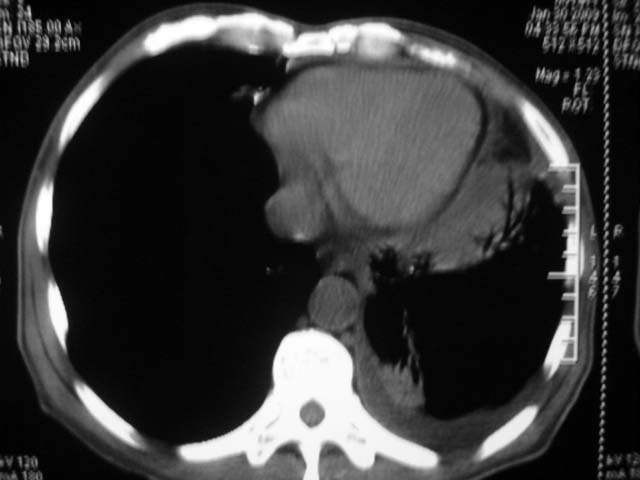

男,52岁,发热2月,糖尿病史。

抗结核治疗irpz方案,血糖未治疗,空腹15.9左右。症状无好转,左胸痛。

复查ct

结果:两肺继发性肺结核并曲霉菌感染。